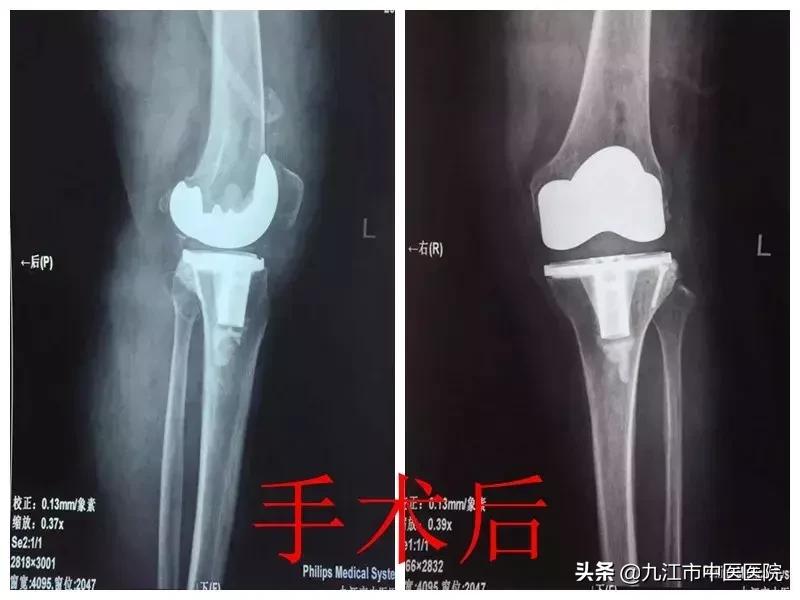

接诊后,王毅带领团队详细分析了该患者相关病史、体征,并行相关影像学检查,经检查发现,该患者为重度膝外翻畸形(股胫角>20°),手术难度较大、风险高。

在和家属充分沟通并取得同意后,经过术前反复论证,最终选择采用适当的截骨与松解技术,根据患者关节稳定程度选择了稳定型膝关节假体。手术非常顺利,术后患者膝关节疼痛减轻,膝外翻畸形纠正,72小时后即可在家人搀扶下下地行走,无任何神经受累症状,目前已恢复正常生活自理活动,正在康复中。